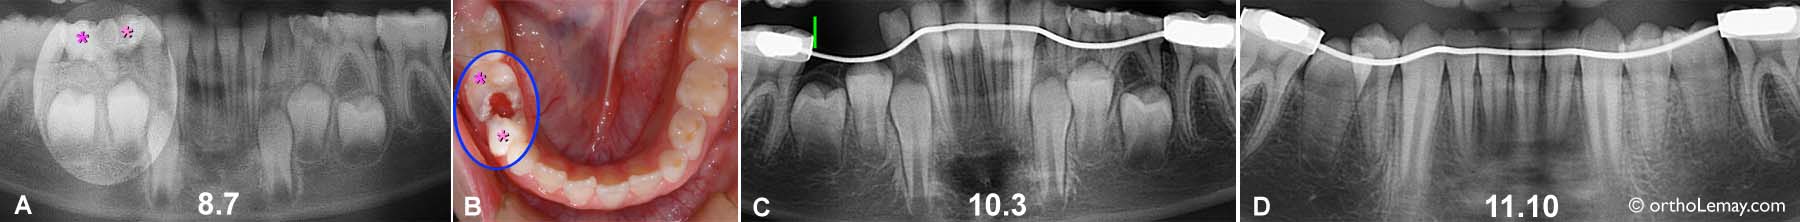

Éruption des dents suite à la pose d’un mainteneur d’espace

La pose d’un mainteneur d’espace suite à l’extraction de dents cariées a permis de préserver l’espace et faciliter l’éruption.

(A, B) Les 2 molaires primaires (*) e ce garçon de 8.7 ans étaient sévèrement cariées et ont dû être extraites.

(C) Un mainteneur d’espace fixe (visible sur la radiographie) fut posé immédiatement après les extractions pour retenir la molaire permanente (ligne verte). 18 mois plus tard une radiographie montre la progression de l’éruption des prémolaires sans qu’il y ait eu perte d’espace.

(D) À l’âge de 11 ans 10 mois, les prémolaires sont sorties de chaque côté de l’arcade. Le mainteneur d’espace a été en place plus de 3 ans mais a permis une éruption la plus normale possible sans perte d’espace et cela des deux côtés. Il manque cependant un peu d’espace pour que les dents soient alignées idéalement mais aucun espace de fut perdu. Le mainteneur peut maintenant être retiré et des corrections orthodontiques entreprises pour corriger la malocclusion s’il y a lieu.